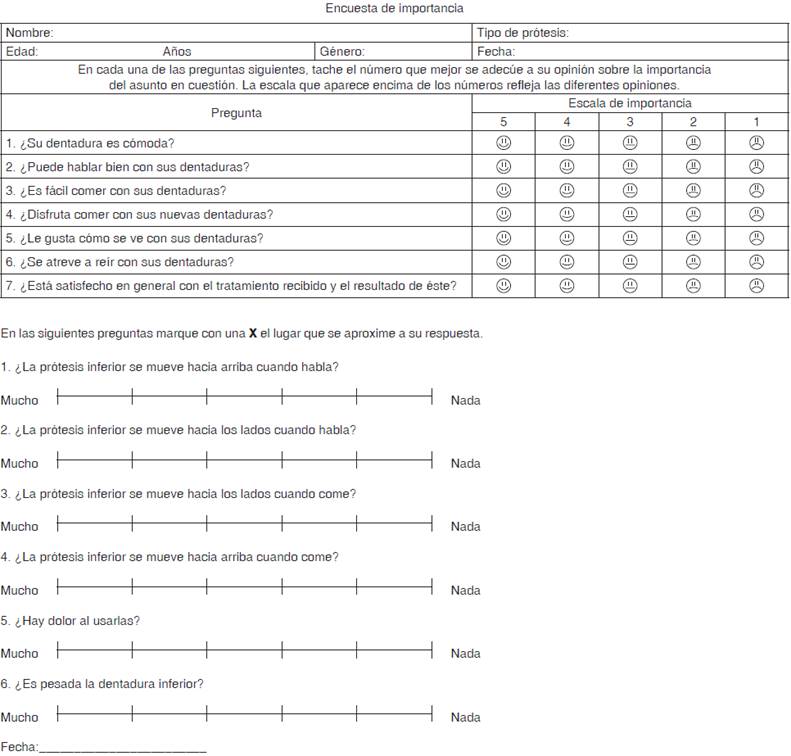

La percepción del paciente fue determinada mediante un instrumento subjetivo de 15 ítems a través de escalas tipo Likert y de una escala visual análoga, evaluando la estabilidad, retención, masticación y conformidad con el tratamiento (Figura 6). Además, se pesó cada tipo de prótesis.

Con relación a la encuesta con preguntas tipo Likert y escala visual análoga (Figura 6), la suma total indica contraste entre ambos tipos de prótesis; las de tipo gravitacional fueron más funcionales (EVA p = 0.043). Las pruebas estadísticas de comparación identificaron principalmente diferencia (p = 0.039) entre la pregunta «movilidad de la dentadura hacia los lados cuando habla», así como «dolor al usarla» indicando más dolor y dificultad para hablar con la dentadura convencional (Figuras 7 y 8).